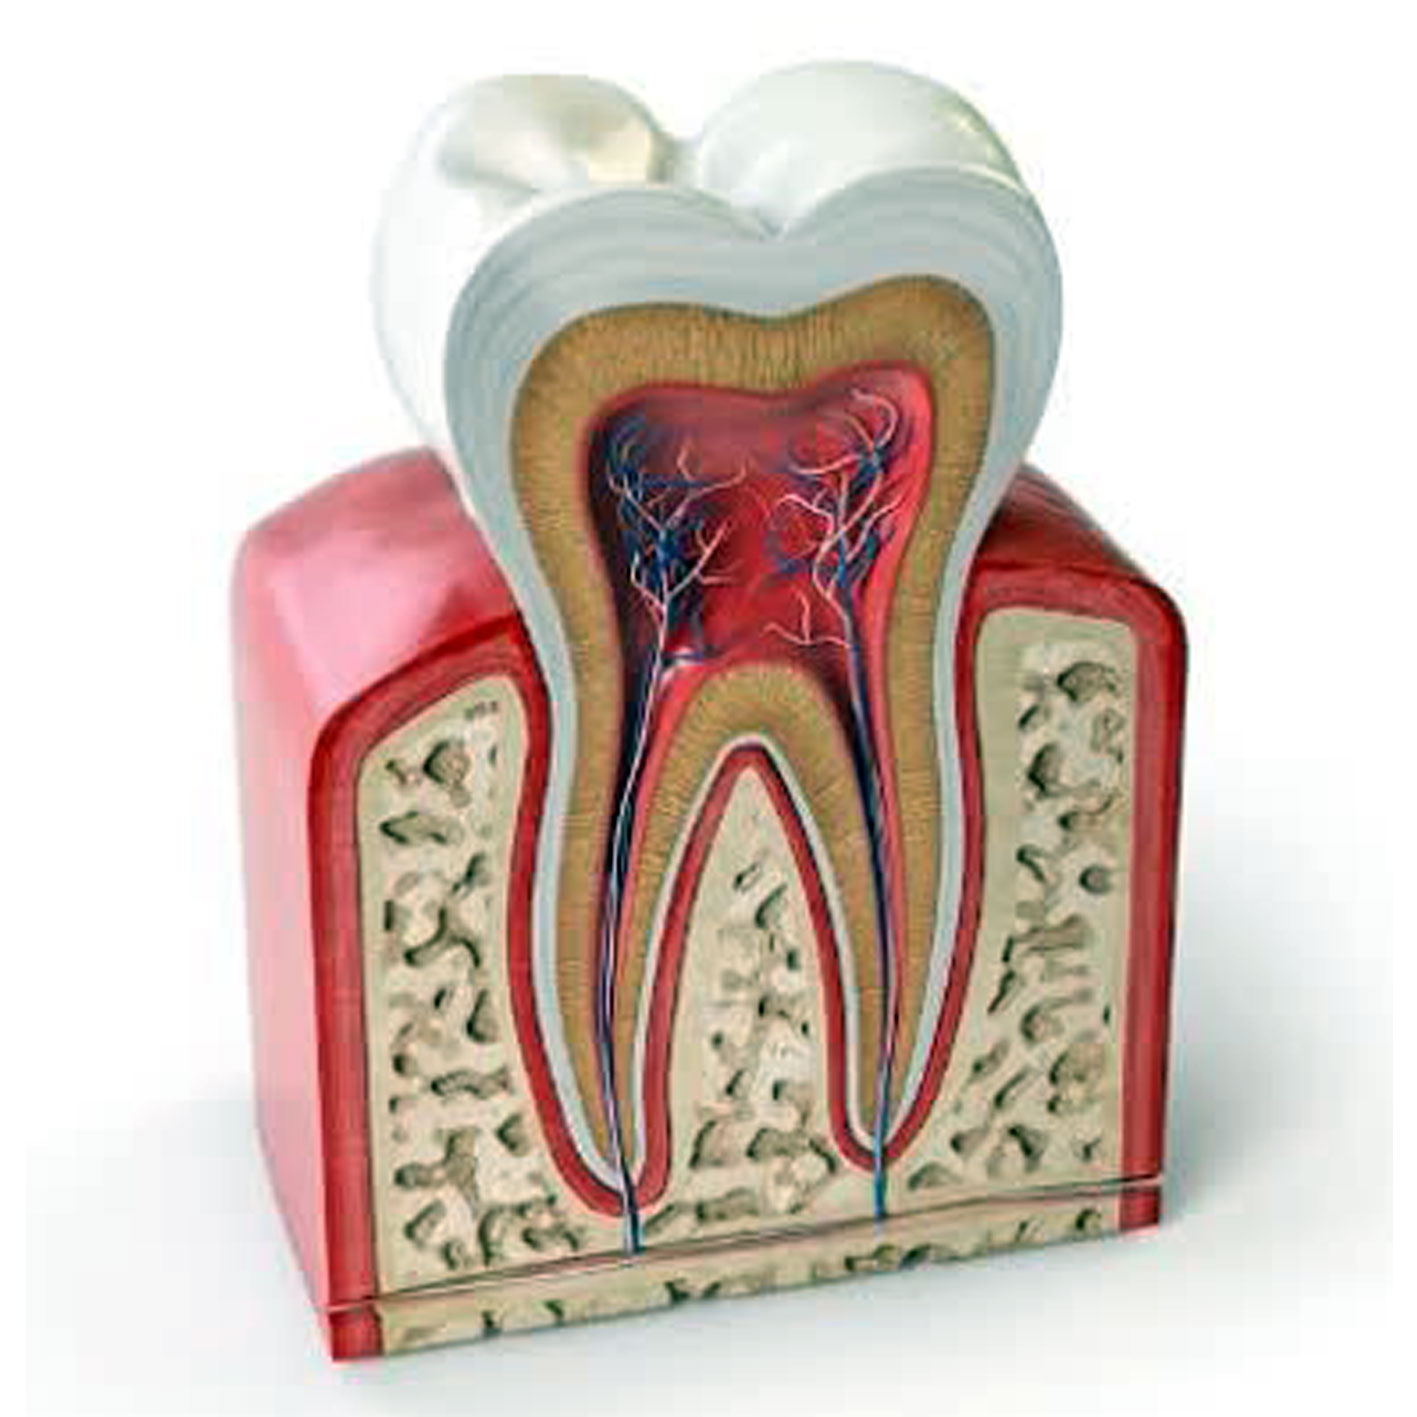

عصب کشی در مواردی انجام می شود که پالپ آسیب برگشت ناپذیر دیده باشد و چاره ای به جز تخلیه و تمیز کردن آن و پر کردن آن با مواد پر کننده مخصوص، وجود نداشته باشد . علت آسیب دیدن پالپ معمولا یکی از موارد زیر است:

پوسیدگی عمیق دندان که درمان نشده و به پالپ رسیده است.